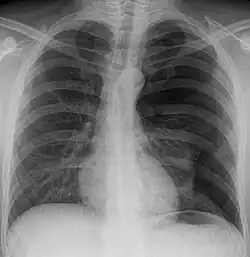

Spontanpneumothorax links

(im Bild rechts)